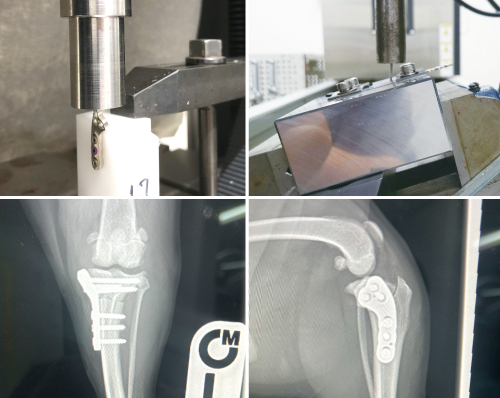

■ 製品の安全性試験

-

小型のTPLOプレートは、極小サイズでありながら高い耐久性と骨との適合性を両立する加工技術が求められました。独自の加工工程を構築し、強度試験・疲労耐久試験を繰り返し開発した製品です。しかし、製品の安全性は、臨床の現場での確認が必要であり専門医による100症例を超える臨床試験を繰り返し、術式、術後の経過を観察することにより製品の安全性を確認を進めています。

3穴タイプのスタンダード仕様ですが、臨床の中で小型の動物では最小骨量でも解剖学的に設置可能な2穴タイプが考案され、選択肢が広げられました。この製品は、臨床現場と開発製造の連携により開発されたTPLOプレートです。製品を届けて終わりとは考えていません。